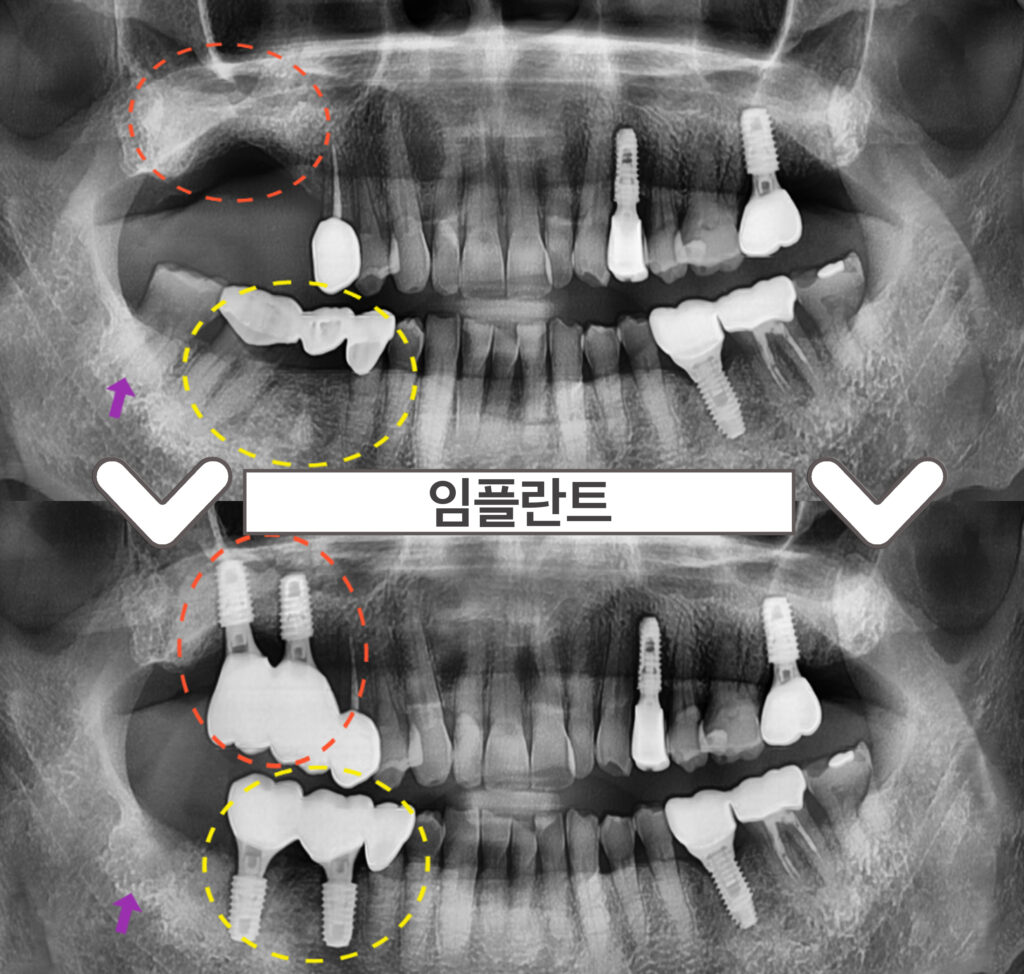

정밀한 검사를 위해

파노라마 사진을 촬영해

확인해 보았더니

노란색 동그라미의

기존 브릿지 보철물 치아 중

두 번째 큰 어금니(#47)가

충치로 인해 치아의 머리 부분과

뿌리가 분리가 된 상태였습니다..!

안타깝지만 살려 쓰기에는

예후가 좋지 않아

발치가 필요한 상황이었는데요.

다행히 두 번째 작은 어금니(#45)는

검진 시 특이 소견이 없어

크라운 치료를 진행하기로 하였답니다.

두 번째 큰 어금니(#47)는 발치하면서

동시에 어금니 자리에 임플란트 2개를

식립하기로 계획하였고,

바로 뒤의 사랑니(#48)도 함께

발치하기로 하였습니다.

그리고 오른쪽 위턱의 어금니는

상실된 상태로

임플란트를 같이 진행을 원하셨는데요.

상실 된 지 오래되어

뼈가 부족한 상황이라,

상악동 거상술을 동반한

임플란트 식립을 계획하였습니다. (2개 식립)

술 후 파노라마와 3D-CT를 통해

발치 후 즉시 임플란트와

상악동 거상술을 동반한 임플란트가

안정적으로 식립된 것을 체크하였답니다.